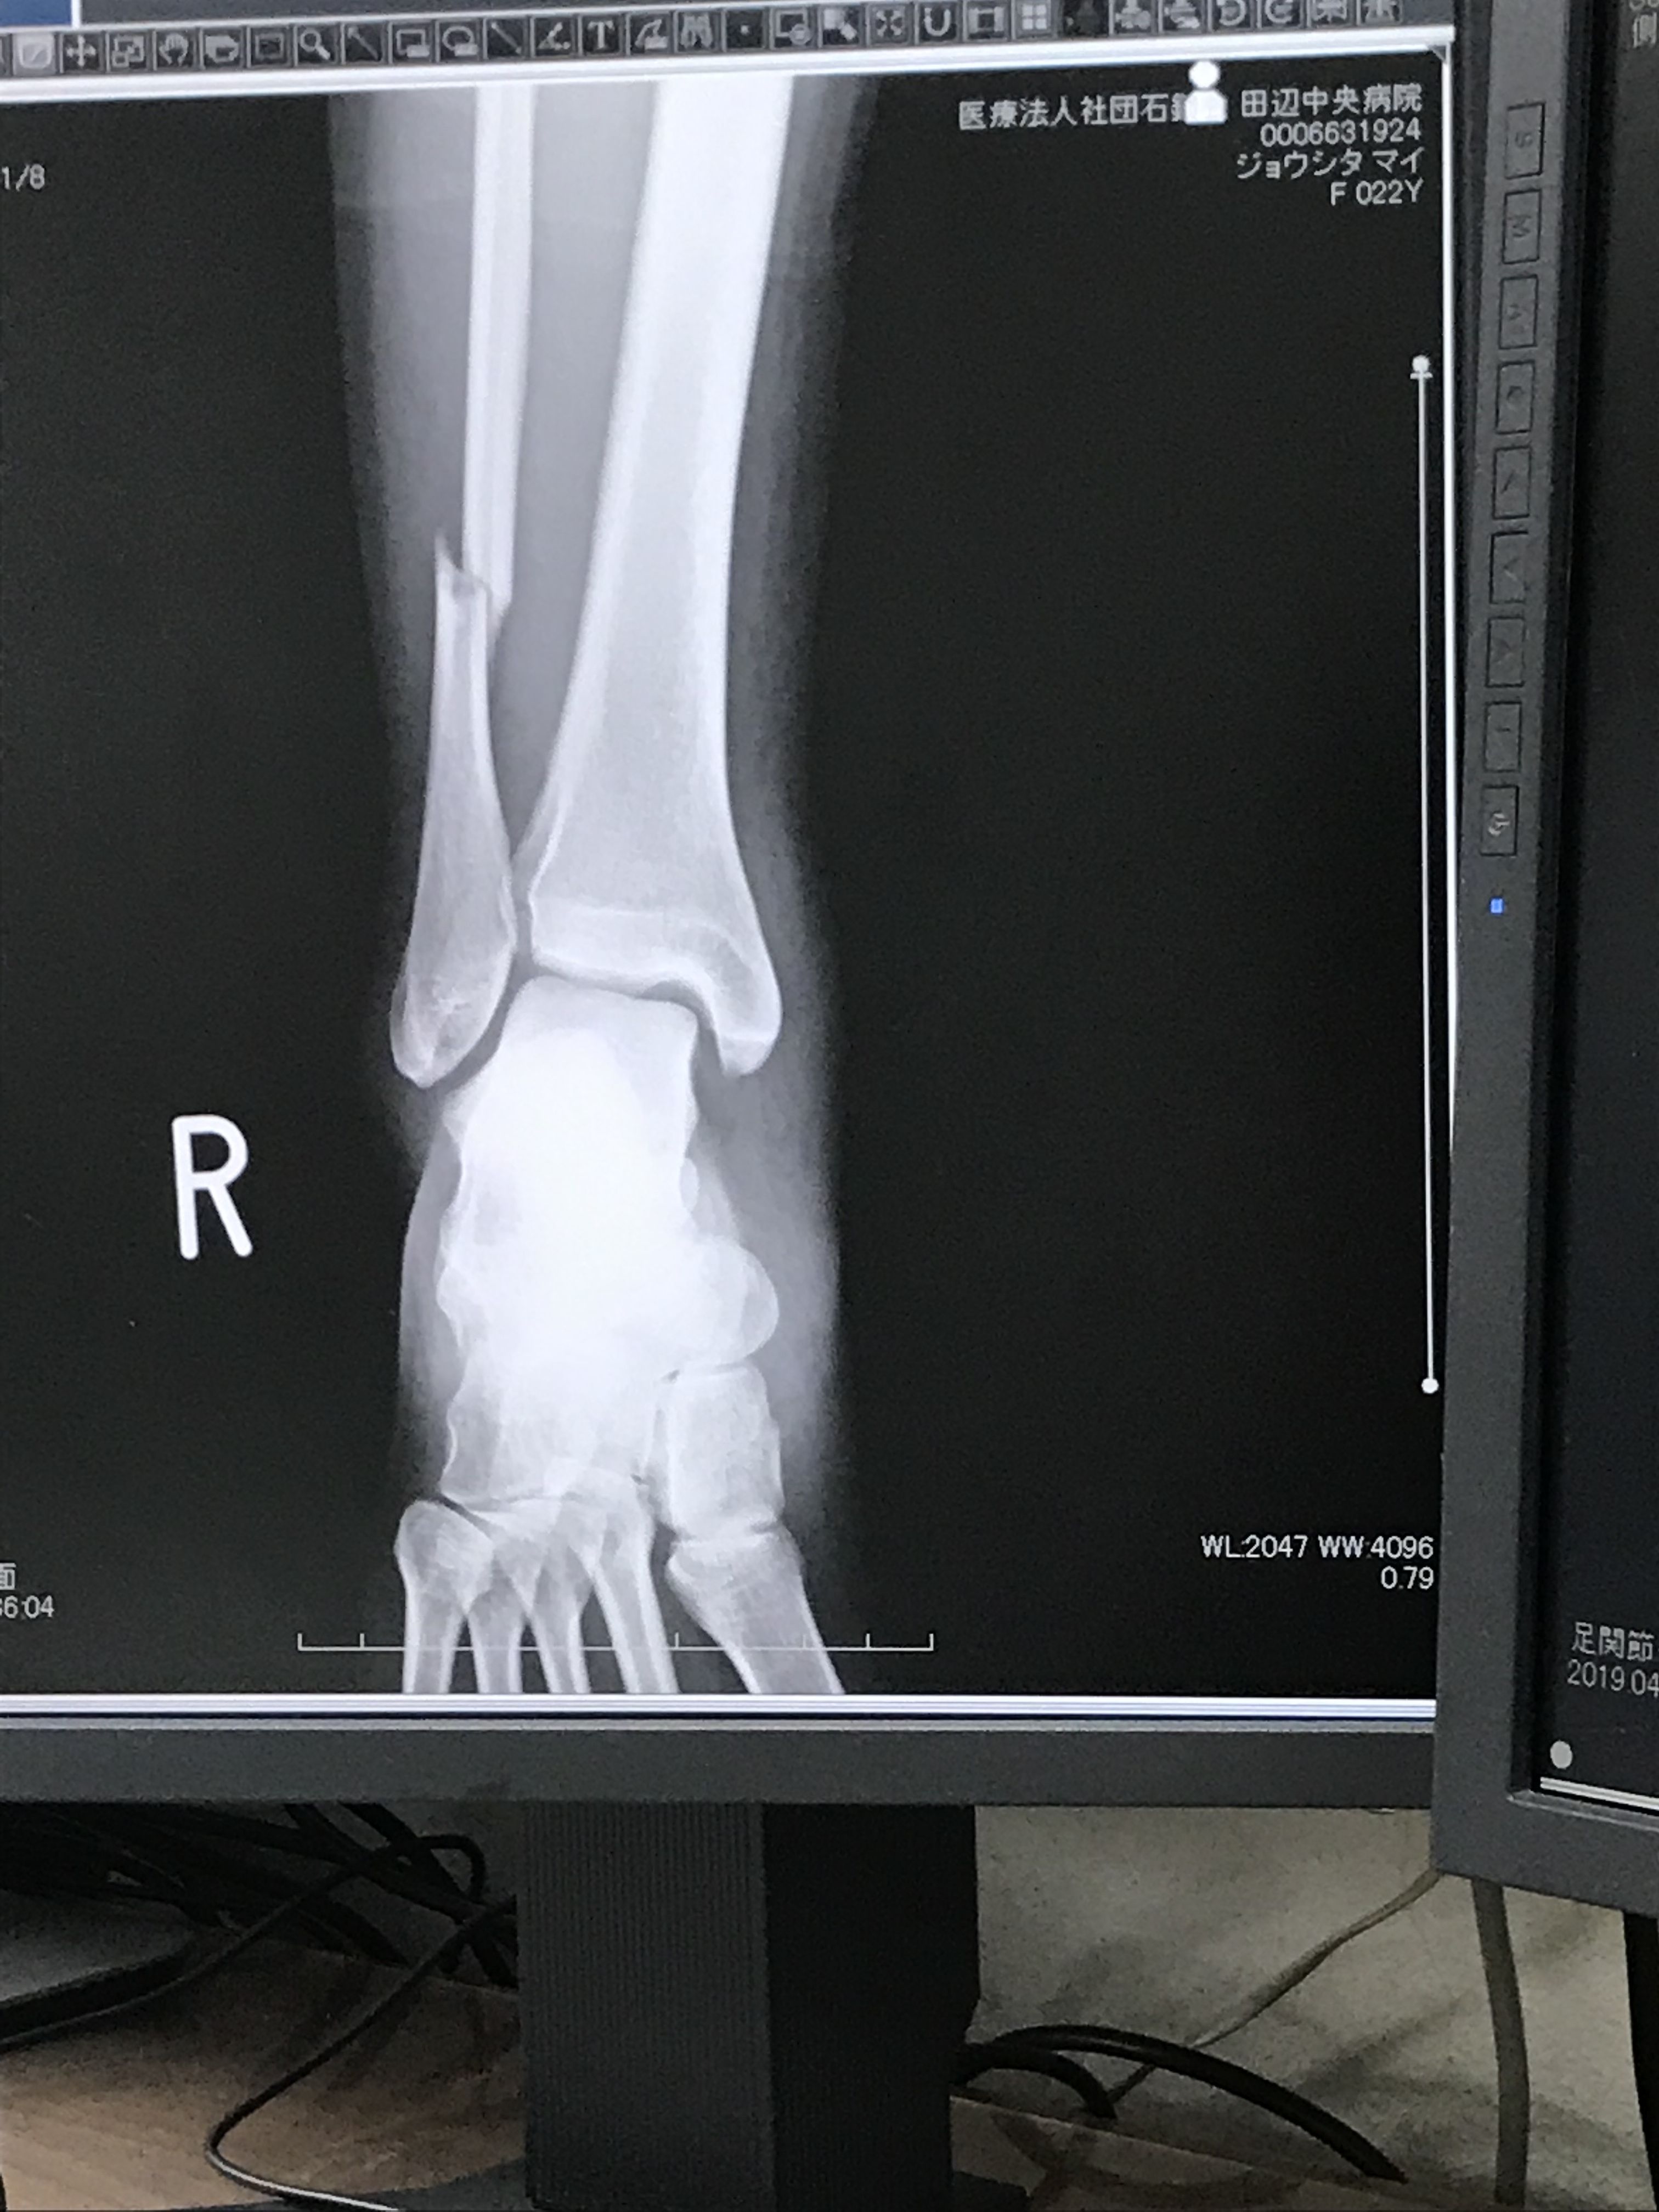

受傷後4週で姿を現した腓骨骨折 整形外科医のブログ

腓骨欠損例の足関節脱臼骨折 整形外科医のブログ